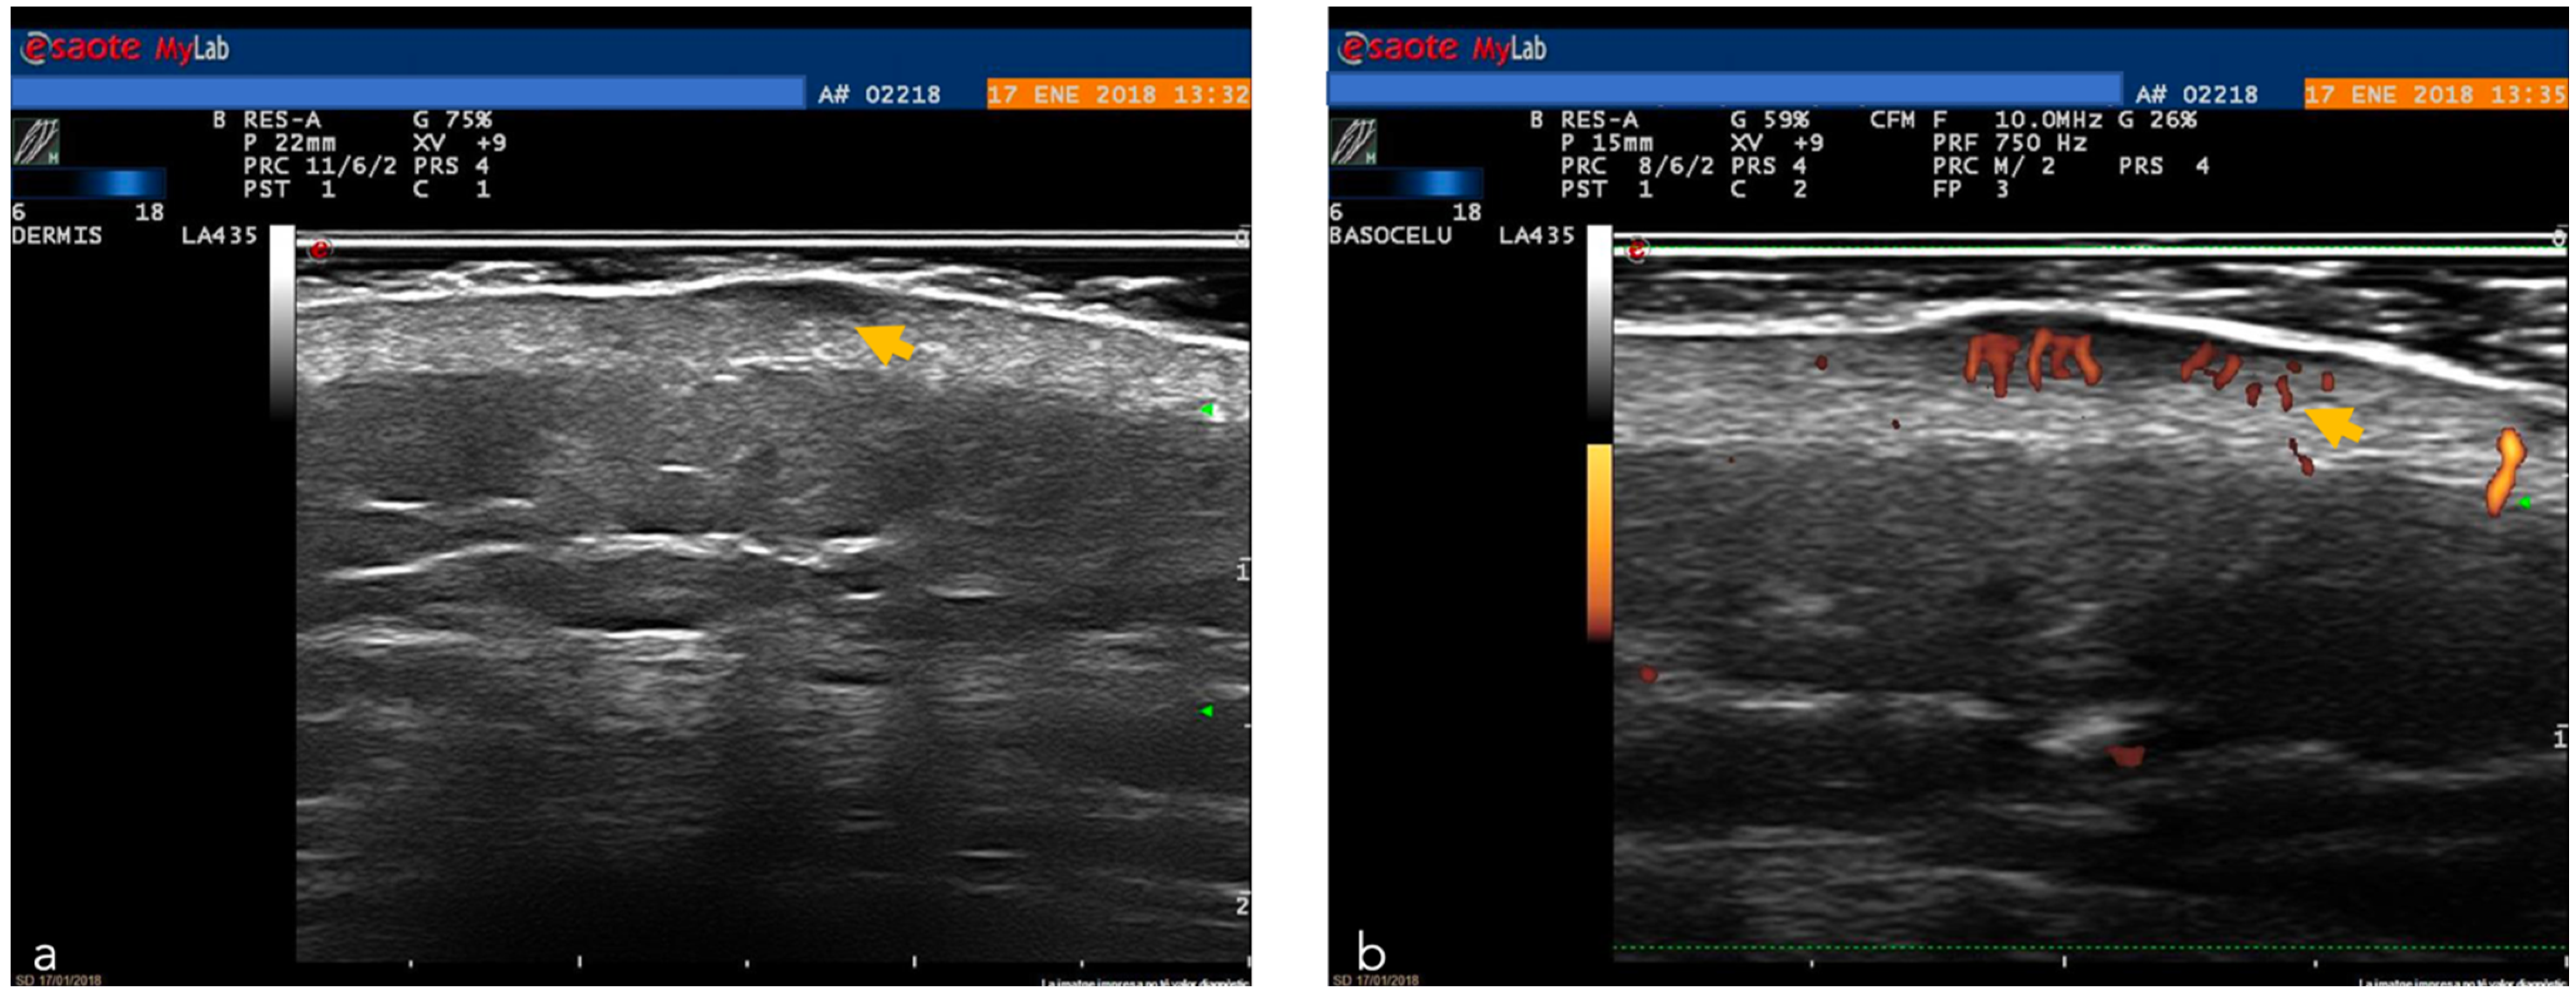

Moreover, ultrasound can aid in the presurgical assessment of other rare tumors such as Merkel cell carcinoma (MC), dermatofibrosarcoma protuberans (DFSP), Kaposi sarcoma and primary cutaneous lymphoma (PCL) [43]. However, the reduced resolution limits the capacity to aid in the diagnosis of different subtypes of malignant skin tumors (e.g., benign vs. melanocytic lesions) [49]. HFUS ultrasound, thanks to its excellent depth of penetration, can be a useful tool in the evaluation of tumor depth and allows pre-surgical planning (Figure 2 and Figure 12) [50].

Figure 12.

High-frequency ultrasound. A probe of 18 MHz: (a) Superficial basal cell carcinoma (yellow arrow); (b) Doppler image (yellow arrow) around the basal cell carcinoma. Image courtesy of Dr. Priscila Giavedoni.